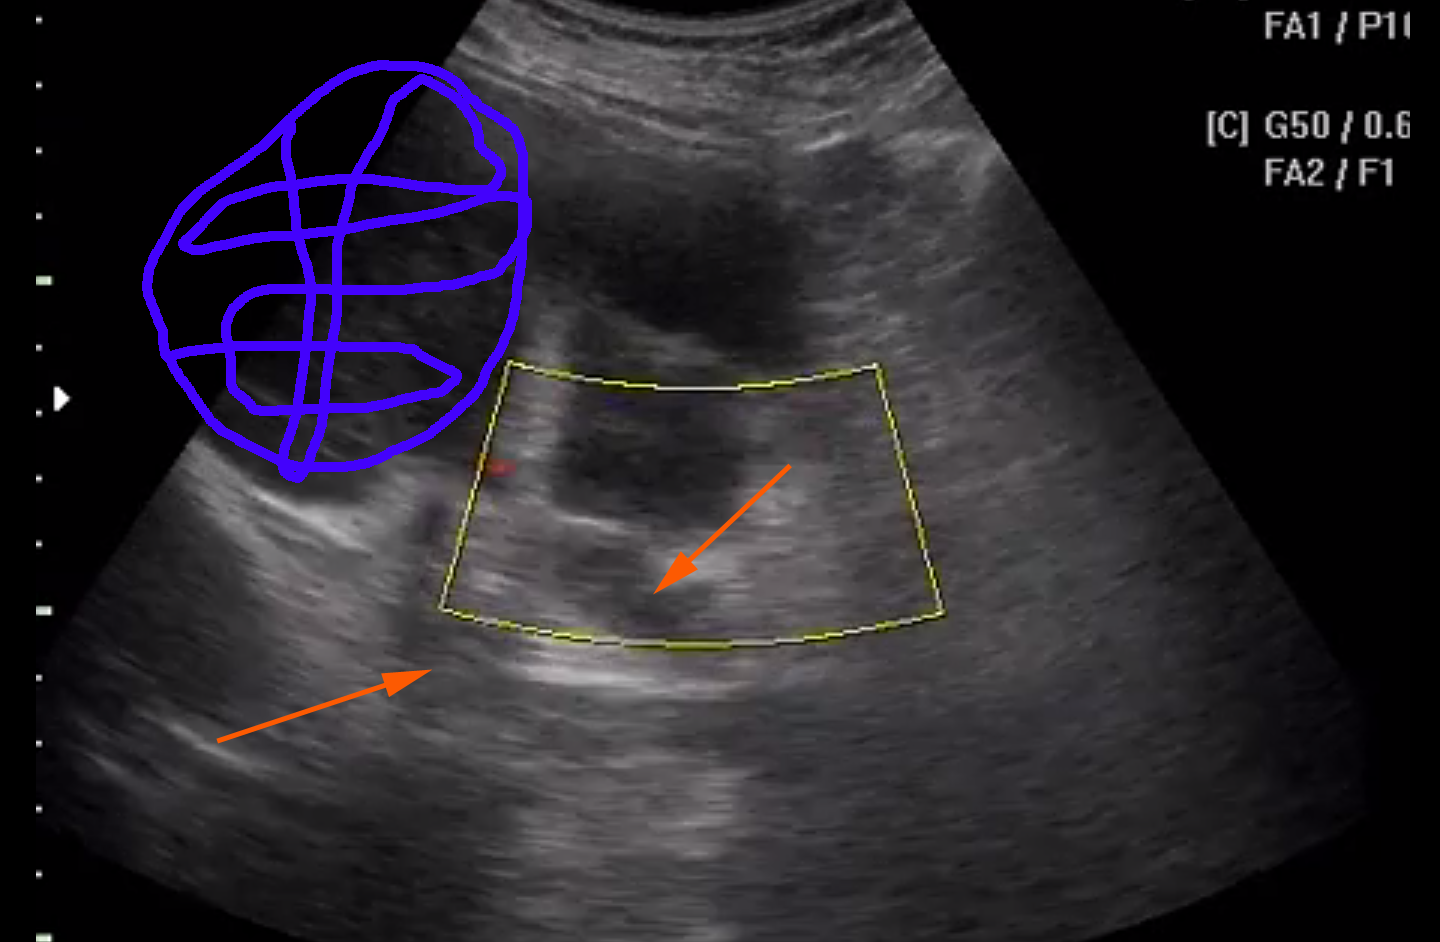

из последнего клипа

Снимок экрана 2015-07-22 в 21.40.52.png

Красная стрелка - сосуд или сосуды, тумор - синий цвет.